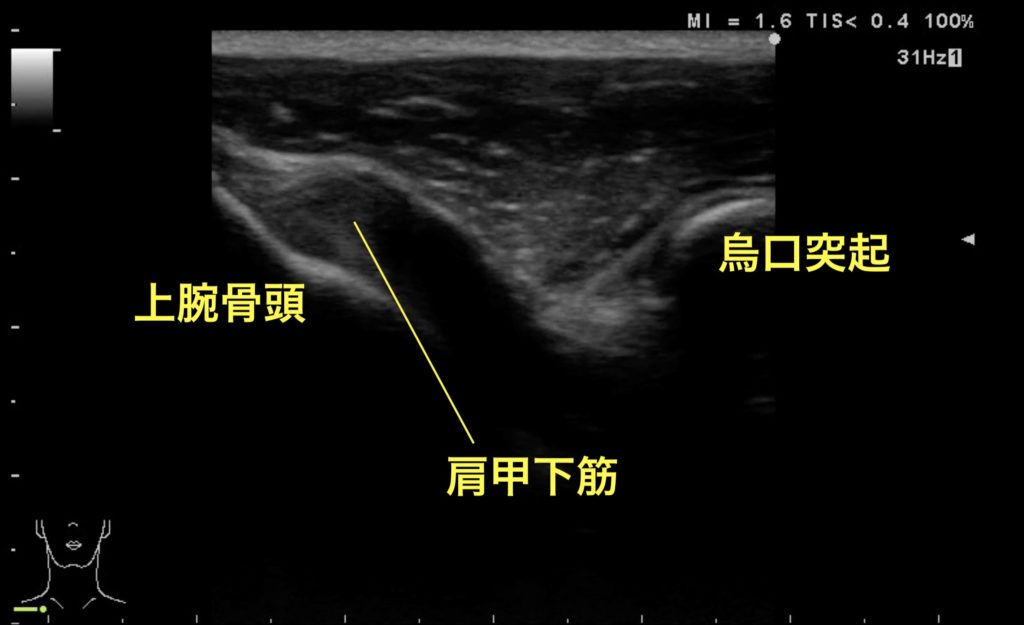

救急外来。右肩打撲。みられる所見はなにか?

肩関節正面像(正常)

肩関節脱臼を評価する際の方法は、正面、側面、後面の3つの方法があるが、正面像では烏口突起と上腕骨頭が水平に同一の高さで描出されることが正常像と判断するための条件である。鎖骨遠位のやや尾側にある烏口突起を触れ、その高さでリニアプローブを水平に当てると、外側に上腕骨頭が描出できる。肩関節脱臼がある場合、変位により烏口突起の外側から骨頭は消失する。